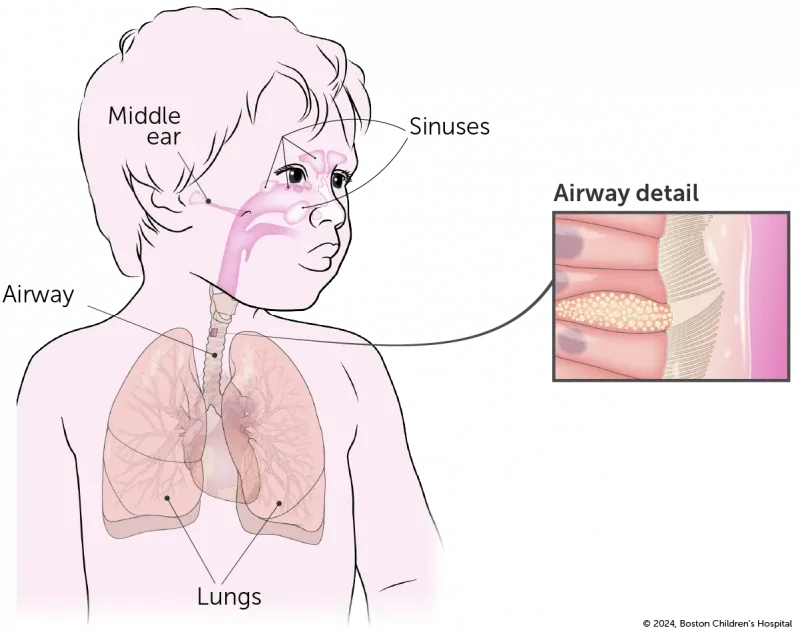

Primary ciliary dyskinesia (PCD) is a disorder of the cilia that line the entire respiratory tract, including the middle ear, sinuses, airway, and lungs, as seen in this illustration.